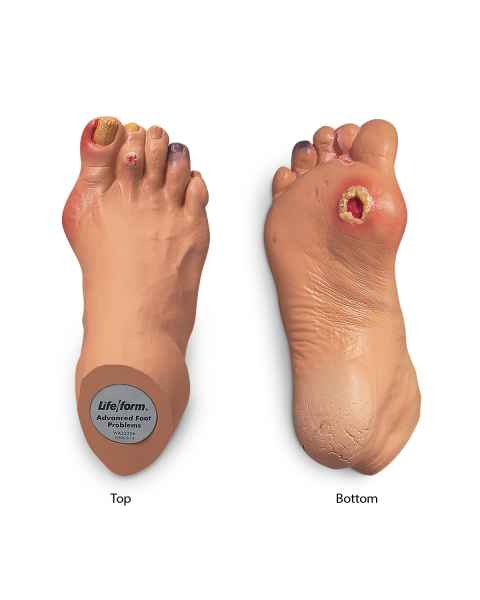

Extremity Models

While the majority of vital human organs are located inside of the head and torso, human appendages are just as important in terms of day-to-day functionality. In order to depict the parts and workings of these limbs, doctors and teachers rely upon extremity anatomical models.

With the assistance of extremity anatomy models, patients and students have a tangible tool to better understand their appendages, as well as potential injuries that are afflicting them or require treatment. Our extensive selection of extremity models includes arm anatomical models, foot models, hand anatomy models, and leg models.